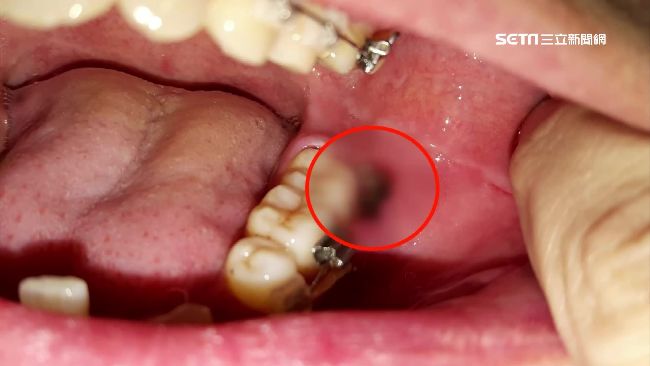

主治醫未操刀?女拔智齒傷口潰爛腐臭

2017/09/25 22:02

台北一名呂小姐投訴,到大醫院拔智齒掛的是陳姓主治醫師的診,當天大部分卻由住院醫師操刀,主治醫師疑似在診間外跟廠商洽談。呂小姐拔完牙後不只臉腫得跟包子一樣,口腔內的傷口還潰爛腐臭,引發蜂窩性組織炎痛到掛急診,他認為主治醫師沒盡督導責任氣得提告。被指控的醫院回應,當天拔智齒的動作確實是由主治醫生操刀,調查後符合規定。